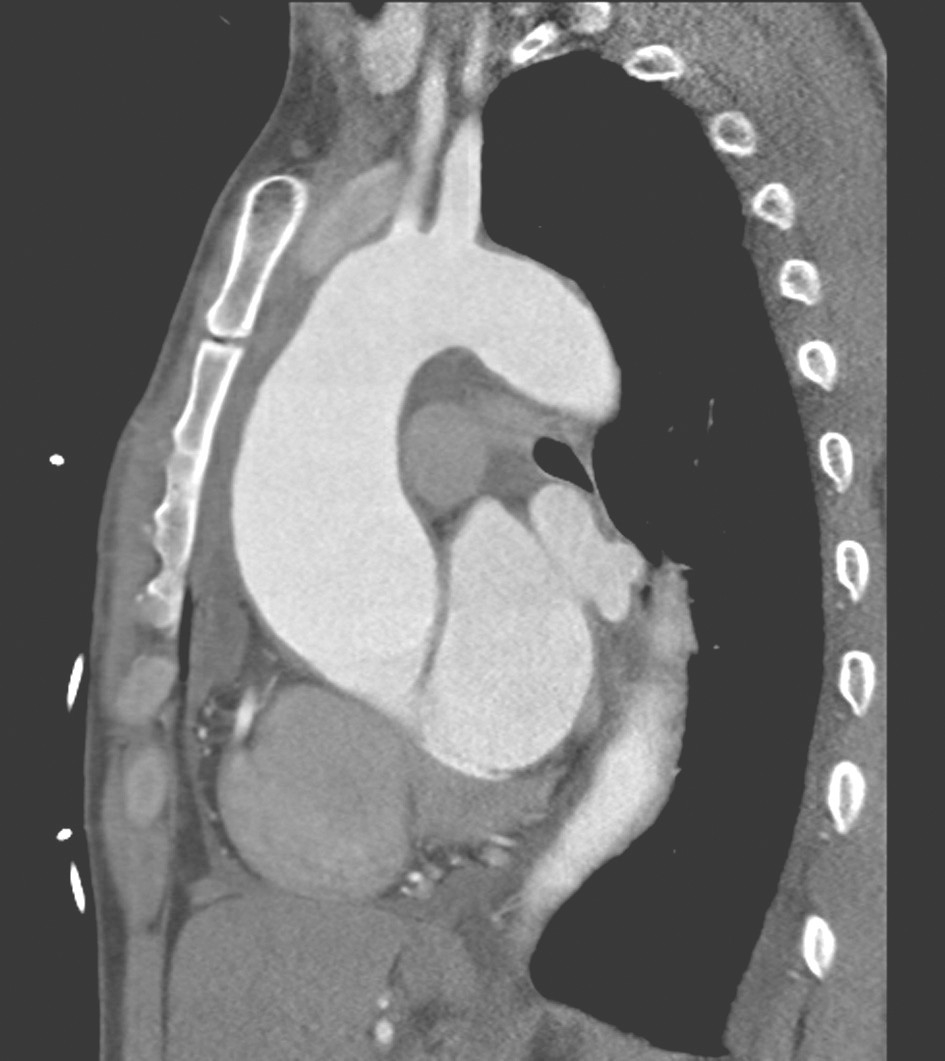

既往检查结果如下:2012年10月,心脏彩超示人工主动脉瓣及管道与主动脉根部前缘可见约直径0.68cm的漏口(图4);左心造影示环主动脉根部假性动脉瘤,漏口位于左前方可能性大;胸主动脉CTA示主动脉瓣区升主动脉根部术区造影剂外渗(图5)。2013年11月,复查胸主动脉CTA提示升主动脉漏口较前明显增大(直径约1.2cm)。2015年5月,心脏彩超示人工主动脉与主动脉前壁间血流信号,考虑术后再次出现瓣周漏(图6);胸主动脉CTA示主动脉根部造影剂漏出,形成一假性动脉瘤,升主动脉上部部分管壁增厚伴溃疡(图7);实验室检查示血沉35mm/h、C反应蛋白35.2mg/dl,抗链球菌溶血素86U/ml,降钙素原正常。

图5 胸主动脉CTA(2012-10)

图7 胸主动脉CTA(2015-05)